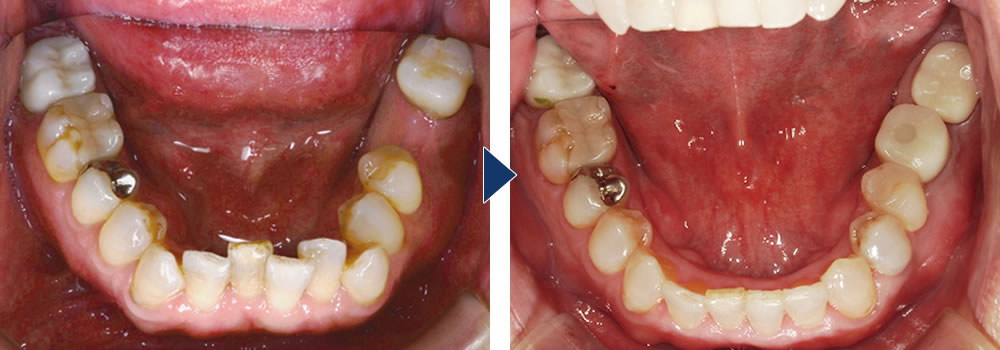

メリット② オープンバイト(開咬)を非抜歯で改善できる

オープンバイトという、奥歯でしか噛み合わない症例では一般的な矯正では、通常前から4番目の歯を抜歯して前方の歯を後ろに引く力を使い、噛ませていく方法をとりますが、MEAW矯正では奥歯を圧下、後方に移動させつつ、前歯を引き出し、噛み合わせることで抜歯を避けることができます。